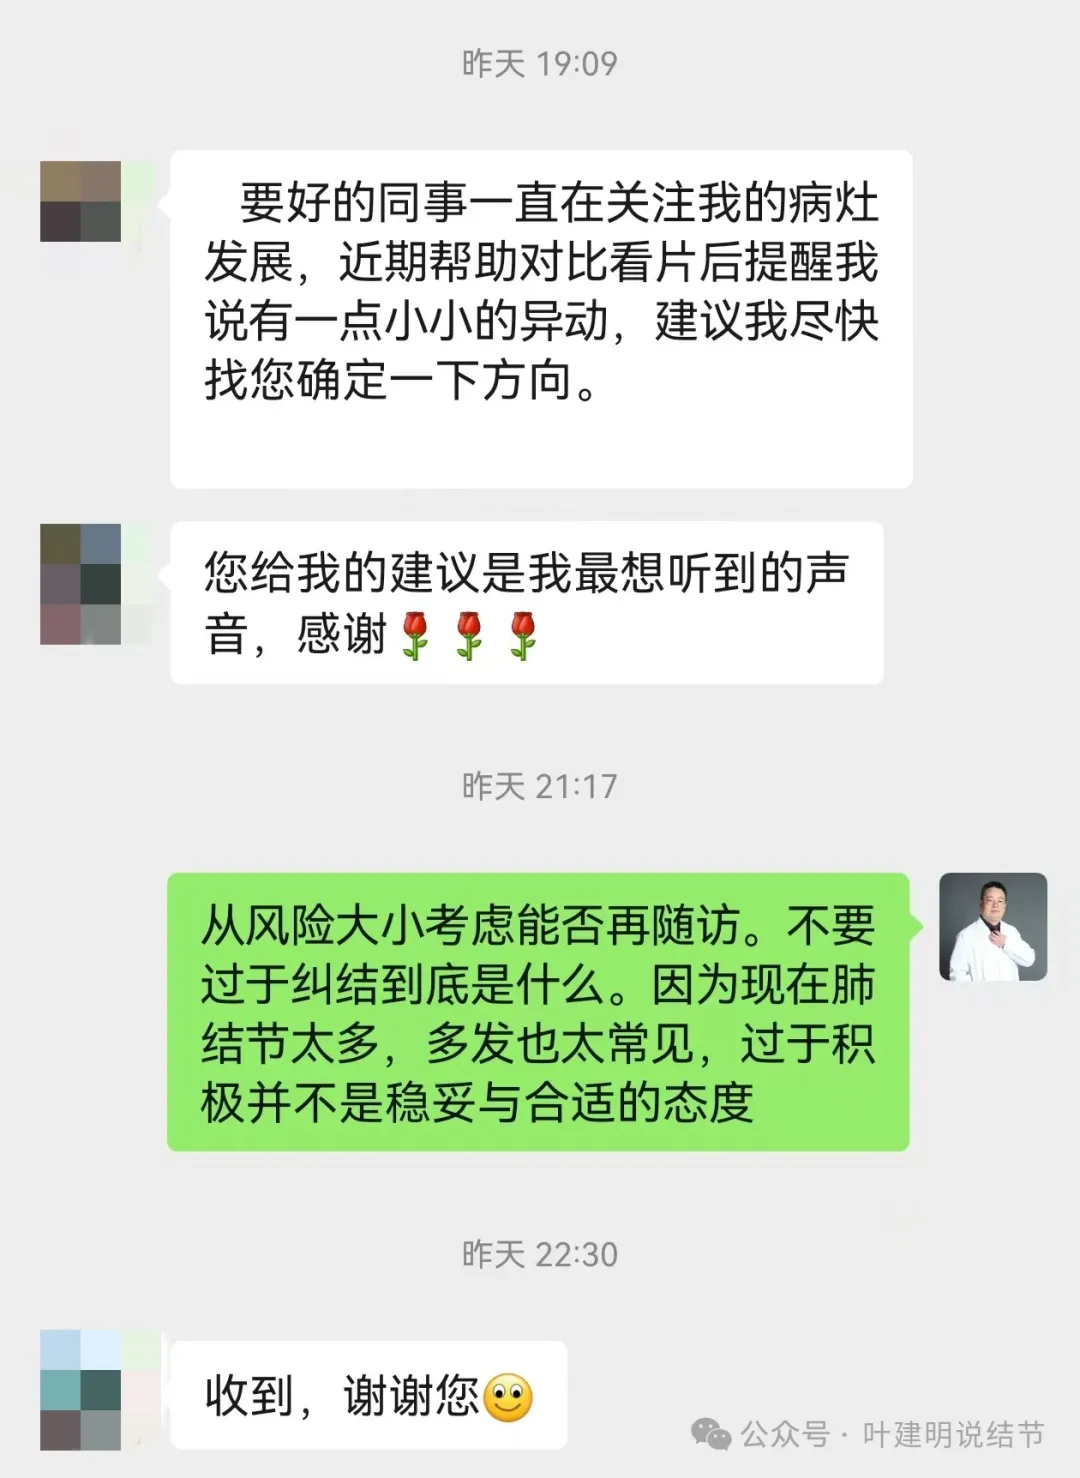

结友同事推荐她看我的文章,复查后又建议她找我确定下该如何。我想当医生,能获得业内同道的认可是最令人鼓舞与欣慰的。也说明我们的坚持努力与付出有价值,有意义。